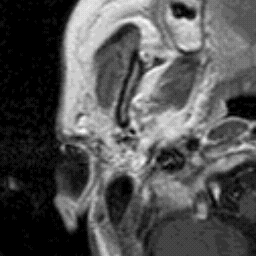

Plate A34: Can You See the Match?